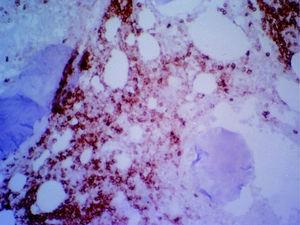

Fig. 5. Cilindro de médula ósea que presenta una celularidad hematopoyética conservada con una buena distribución entre el parénquima y la grasa con presencia de las tres series que muestran una arquitectura dentro de los límites de la normalidad. Se identifican megacariocitos de pequeño tamaño y núcleo hipercromático. Focalmente se observa infiltración del espacio medular por una celularidad linfoide de gran tamaño, núcleo vesiculoso, cromatina grumosa y nucleolo prominente que se dispone formando un nódulo paratrabecular.

Fig. 6. Estudio de inmunohistoquímica sobre material parafinado en el que se observa que la celularidad linfoide de gran tamaño descrita resulta positiva para marcadores Pan-B (CD20) y negativos para marcadores Pan-T (CD3). El índice de proliferación en la celularidad linfoide medido como positividad nuclear con Mib-1 es superior al 75% de las células.